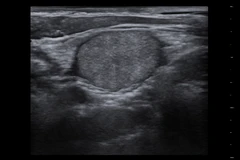

USG Tiroid – pemeriksaan pencitraan dengan gelombang ultrasonik untuk melihat ukuran, bentuk, dan kondisi kelenjar tiroid di leher.

Tiroid adalah sebuah kelenjar yang berfungsi untuk pengaturan metabolisme tubuh. Kelenjar tiroid memproduksi hormon untuk membantu mengendalikan sel dan jaringan dalam tubuh.

Tiroid memiliki dua hormon yang paling penting, yaitu thyroxine (T4) dan triiodothyronine (T3). Jika kadarnya meningkat, maka dapat menyebabkan hipertiroidisme. Sedangkan jika produksi hormonnya terhambat, maka bisa memicu hipotiroidisme.

Fungsi pemeriksaan tiroid

- Mengetahui struktur maupun fungsi kelenjar tiroid

- Mendeteksi penyakit di kelenjar tiroid